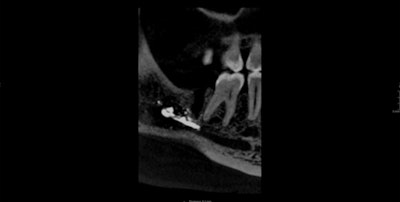

Imaging showed that root canal sealer was widespread within the marrow spaces where endodontic treatment had occurred. The sealer extended to the mandibular canal and perforated the mandible's lingual cortex. There was also evidence of bony destruction and periosteal reaction.

A cone-beam computed tomography (CBCT) scan confirmed widespread extrusion of the root canal sealer in this region. Upon surgical exploration and decompression of the woman's right inferior alveolar nerve, clinicians found an avascular and fibrotic nerve with virtually no normal neuronal structure. They also saw evidence of foreign material, which was found to be root canal sealer, in contact with the epineurium and within the nerve trunk.